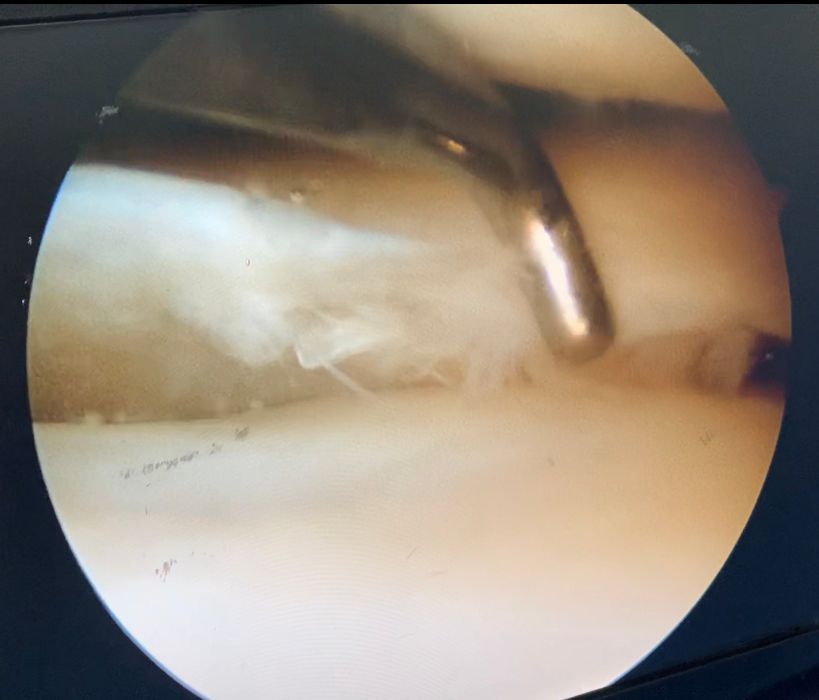

•Grande experiência em videoartroscopias para tratamento de lesões traumáticas e ligamentares de joelho, ombro e cotovelo.

- Ruptura do manguito rotador

Ruptura do manguito rotador

Se você tem percebido uma diminuição da força do ombro, dificuldade para movimentá-lo ou carregar objetos, além de dores que podem irradiar desde a região escapular, para o braço ou para a região do pescoço, fique atento! Podem ser sintomas da lesão do manguito rotador. O manguito rotador é uma estrutura que envolve a cabeça do úmero, parte superior do osso do braço, que se articula à escápula. Sendo responsável pela estabilidade articular do ombro e pelos movimentos desta área. Essas lesões podem acometer pessoas de diferentes idades. As principais causas são: a degeneração dos tendões pelo avanço da idade, o esforço repetitivo com impacto articular, e os traumas.